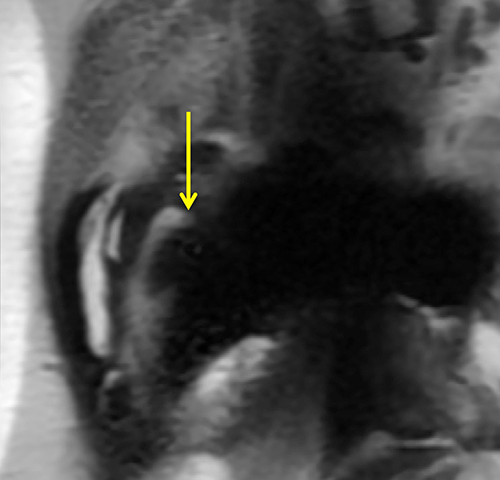

Hip Prosthesis Conventional

In conventional T2-weighted image, metal artifact obscures osteolysis (yellow arrows).